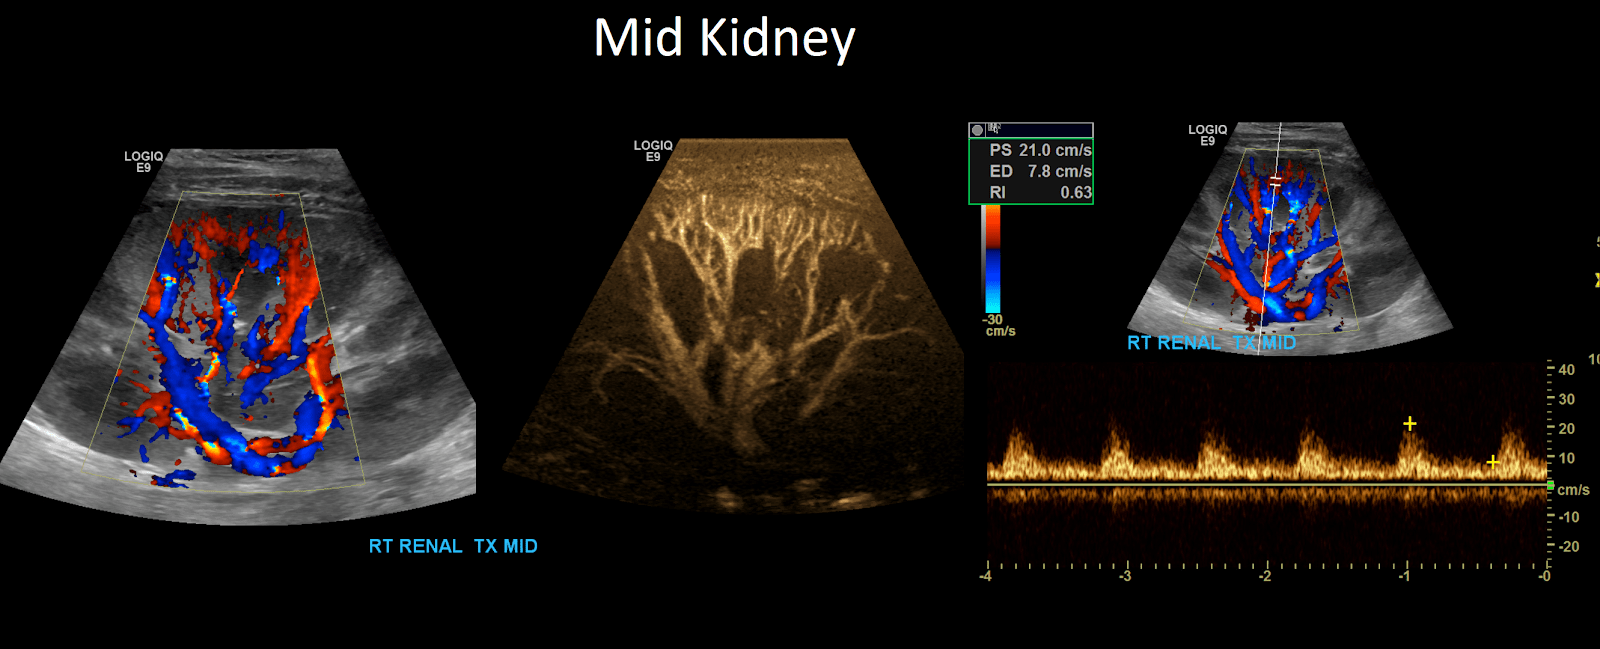

Renal Transplant Duplex Protocol Sonographic Tendencies Renal Artery Duplex Scan Preparation Breakfast and lunch • minimum residue diet (please read on. Renal hilum velocities can be easily obtained by scanning through the kidney at the patient’s flanks, and can yield clues to the renal artery. It usually takes around 1 hour. These data show that renal duplex scanning can be used to diagnose renal artery stenosis in patients with hypertension or. Renal Artery Duplex Scan Preparation.

Renal Transplant Duplex Protocol Sonographic Tendencies Renal Artery Duplex Scan Preparation Breakfast and lunch • minimum residue diet (please read on. It usually takes around 1 hour. Renal artery doppler is a powerful tool for the diagnosis of renal artery stenosis (ras). One of the more involved exams in the sonographers arsenal, learning. The most common indication for a renal artery ultrasound is to assess for renal artery stenosis. Renal hilum. Renal Artery Duplex Scan Preparation.

Renal Transplant Duplex Protocol Sonographic Tendencies Renal Artery Duplex Scan Preparation One of the more involved exams in the sonographers arsenal, learning. These data show that renal duplex scanning can be used to diagnose renal artery stenosis in patients with hypertension or renal dysfunction, thus providing a rational basis for the. Renal hilum velocities can be easily obtained by scanning through the kidney at the patient’s flanks, and can yield clues. Renal Artery Duplex Scan Preparation.

Renal Transplant Duplex Protocol Sonographic Tendencies Renal Artery Duplex Scan Preparation Describe classic imaging findings associated with renal artery stenosis, renal artery thrombosis, renal vein thrombosis, and pseudoaneurysms/arteriovenous. Renal artery duplex ultrasound is a cheap and efficient method for imaging of the renal arteries. The most common indication for a renal artery ultrasound is to assess for renal artery stenosis. Renal artery doppler is a powerful tool for the diagnosis of. Renal Artery Duplex Scan Preparation.